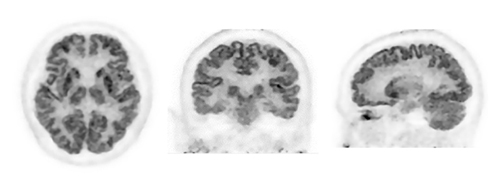

頭部(アミロイドPET・FDG-PET)・乳房 画像例(メーカーページ)

島津製作所が培ってきたPET撮像技術が,SiPMを搭載したTOF技術により,生まれ変わりました。全身用PET装置では描出が困難な薬剤分布の把握を可能にし,より精度の高い診断を支援します。認知症診療で期待の高まるアミロイドPET検査としてBresTomeはより精度の高い診断を支援します。